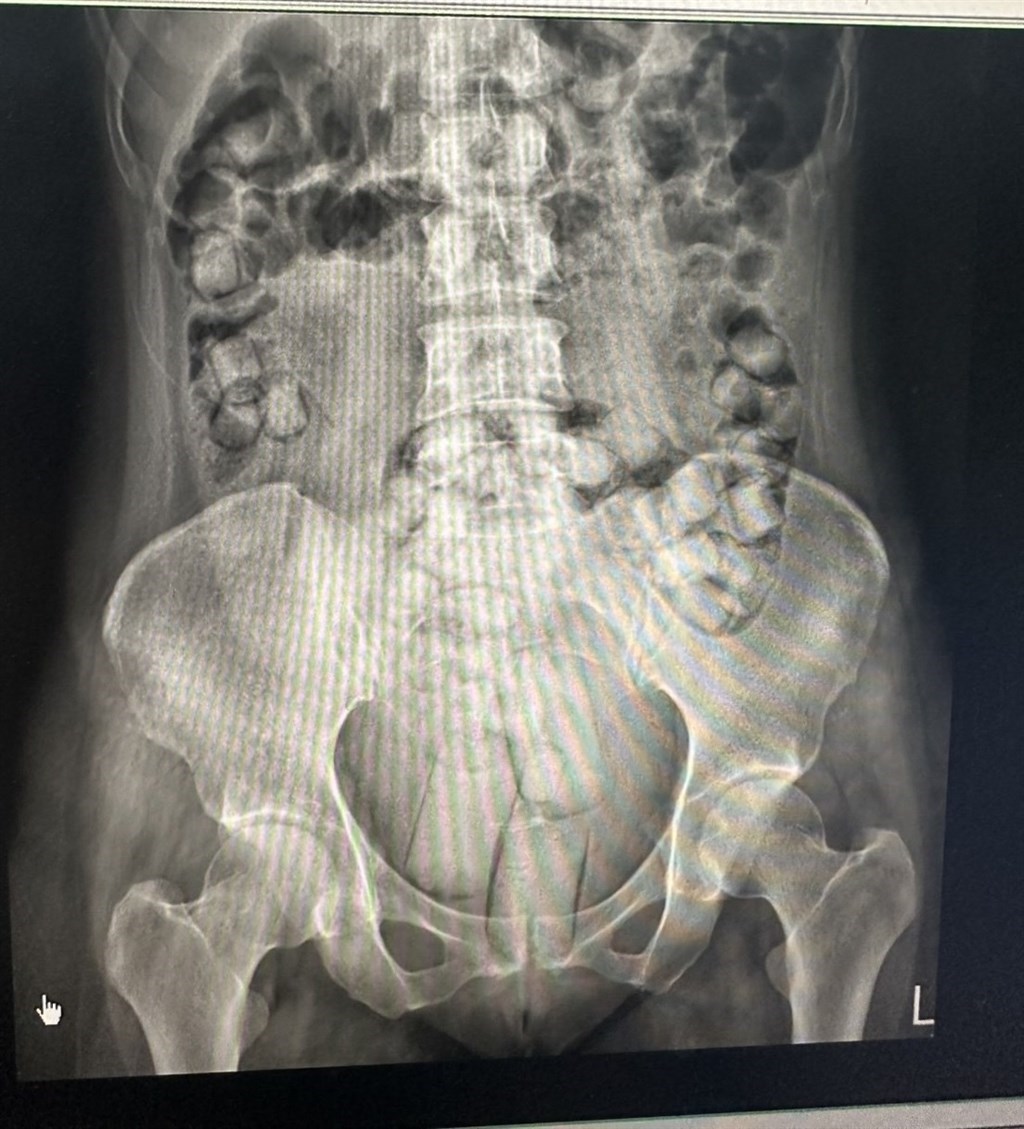

Keduanya ditangkap tim Direktorat Jenderal Penjaga Pantai Taiwan saat tiba di imigrasi Bandara Internasional Kaohsiung. Hasil pemeriksaan sinar-X menunjukkan adanya benda padat dalam jumlah besar di dalam tubuh mereka, yang setelah dikeluarkan dan diuji, teridentifikasi sebagai heroin, kata pengadilan.